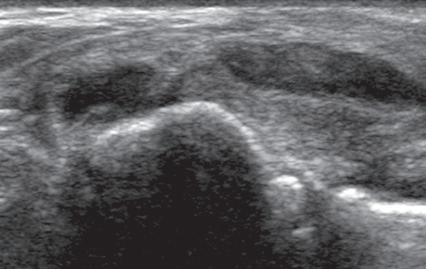

is fusion imaging, in which real-time ultrasound imaging can be superimposed on computed tomography (CT) or MRI; this has been used to assist with needle guidance for sacroiliac joint injections.17 One last technique is sonoelastography, which is used to assess the elastic properties of tissue. The three types of sonoelastography include compression elastography (using manual compression), shear wave elastography (using a directional shear wave), and transient elastography (using a short pulse).18 With compression elastography, manual compression of tissue produces strain or displacement within the tissue. Displacement is less when tissue is hard; it is displayed as blue on the ultrasound image, whereas soft tissue is displayed as red (Fig. 1.27). With regard to musculoskeletal applications, normal tendons appear as blue, whereas areas of tendinopathy, such as of the Achilles tendon or common extensor tendon of the elbow, appear as red.16,19-22 With shear wave and transient elastography, the velocity of the shear wave is measured to determine elasticity and has the advantage of less operator dependence and ability to produce qualitative and quantitative information.18,23

area below white arrow). Note that hard tissues are displayed in blue and soft tissues in red. (Courtesy